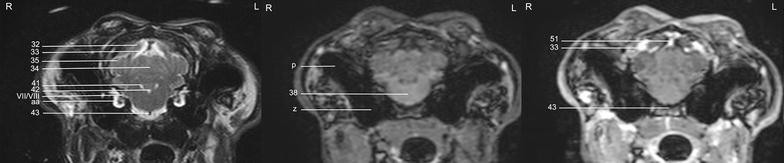

Magnetic Resonance Imaging Anatomy Of The Rabbit Brain At 3 T | Acta

Magnetic resonance imaging anatomy of the rabbit brain at 3 T | Acta actavetscand.biomedcentral.com

brain anatomy resonance fig rostral transverse